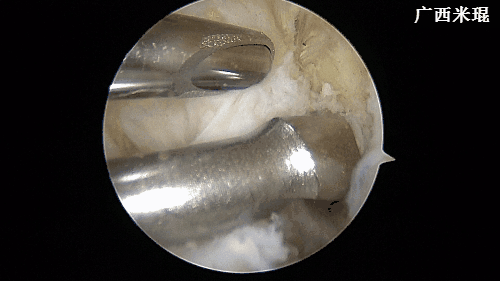

(七)清理髁间窝

维持膝关节屈曲90度,关节镜监视下建立偏高位的前内入路,置入关节镜刨刀及等离子刀,清除髁间窝滑膜、ACL残端,显露髁间窝外侧壁的后方,用等离子刀标注ACL胫骨隧道及股骨隧道内口。然后在关节镜监视下建立前内入路内下方的辅助入路。此操作2分钟内完成。